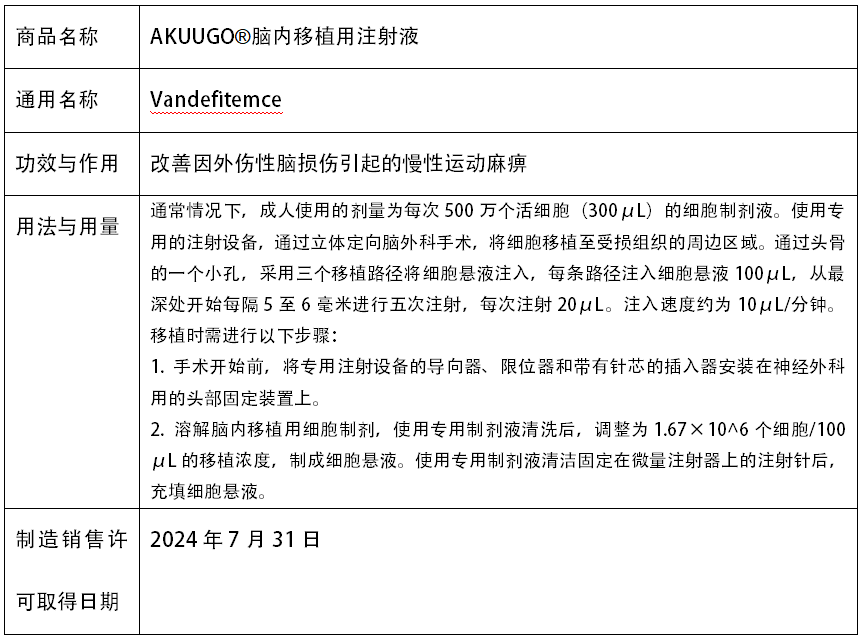

干細胞治療慢性運動癱瘓:2024年6月,全球首個治療慢性運動癱瘓的間充質干細胞療法獲批上市,AKUUGO?腦內移植用注射液”在日本獲得條件性和限時性上市批準,用于改善由創傷性腦損傷(TBI)引起的慢性運動癱瘓。